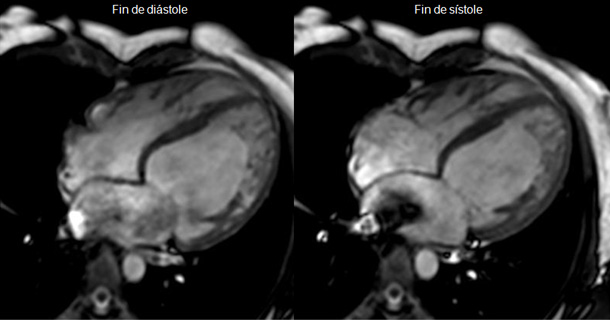

Evaluación funcional y anatómica

Mediante secuencias morfológicas (spin echo) y funcionales de cine-RM (gradient echo), proporciona información precisa acerca de:

-Dimensiones de cavidades cardiacas

– Grosor parietal

– Masa ventricular

– Volúmenes

– Función sistólica ventricular, global y segmentaria.

– Funcion diastolica.